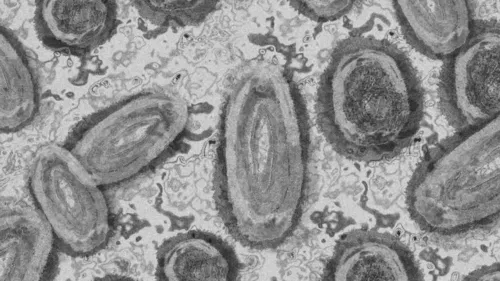

Os Estados Unidos registraram os primeiros casos de varíola dos macacos em crianças. A informação foi dada pela diretora do Centro para Controle e Prevenção de Doenças (CDC), Rochelle Walensky, em entrevista ao jornal Washington Post, na sexta-feira (22). São duas crianças infectadas, sendo que uma delas ainda é uma criança de colo, em casos não relacionados.

Segundo o CDC, a contaminação ocorreu dentro de casa, mas as autoridades ainda estão apurando como isso ocorreu. Uma das crianças não mora nos Estados Unidos. Ela e os pais estavam em viagem pela capital Washington. Já a criança de colo mora na Califórnia. As crianças, acrescentou a diretora do CDC ao Washington Post, passam bem e estão sendo submetidas ao tratamento antiviral.

Nos dois casos, relatou Rochelle, as crianças tiveram contato com homens da comunidade gay. Esse grupo é o mais afetado pela varíola dos macacos e a maior causa de preocupação das organizações de saúde. Inclusive, uma das preocupações da Organização Mundial de Saúde (OMS) é com o estigma que a doença pode provocar em homossexuais do sexo masculino. A entidade, inclusive, já tem pedido ajuda de organizações da sociedade civil, incluindo aquelas com experiência no trabalho com pessoas HIV positivo, para combater a discriminação.

No sábado (23), o diretor-geral da OMS, Tedros Adhanom, declarou que a varíola dos macacos configura emergência de saúde pública de interesse internacional. Ainda que tenha sido uma decisão unânime dentro do comitê de emergência da OMS, o diretor-geral entendeu que já existem elementos suficientes para enquadrar a varíola dos macacos nessa categoria.